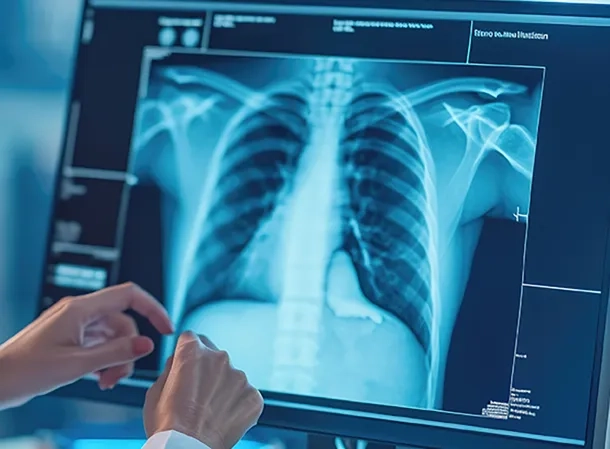

Vous souhaitez améliorer votre efficacité opérationnelle et optimiser la sécurité de vos patients en vous équipant d’équipement de radiologie conventionnelle ? Profitez de ce marché pour acquérir des capteurs plans numériques mutualisables avec les équipements radiogénes installés ou à venir ainsi que des équipements de radiologie conventionnelle innovants adaptés à vos besoins.

Amélioration de la prise en charge patient :

- Optimisation du parcours de soin

- Une offre 360° répondant à tous les utilisateurs

- Diminution et optimisation de la dose injectée au patient

Pour les radiologues :

- Aide au diagnostic – Logiciels d’IA

- Qualité de la chaine d’image

- Le lot 3 permet une évaluation dynamique au lit du patient, ce qui n’était pas possible précédemment. Il permet de préserver le confort du patient en évitant sa mobilisation.

- Le lot 4 permet d’anticiper certains examens d’imagerie en préhospitalier, avant l’arrivée aux urgences des patients, des patients alités et éloignés et pour les usages de médecine légale.